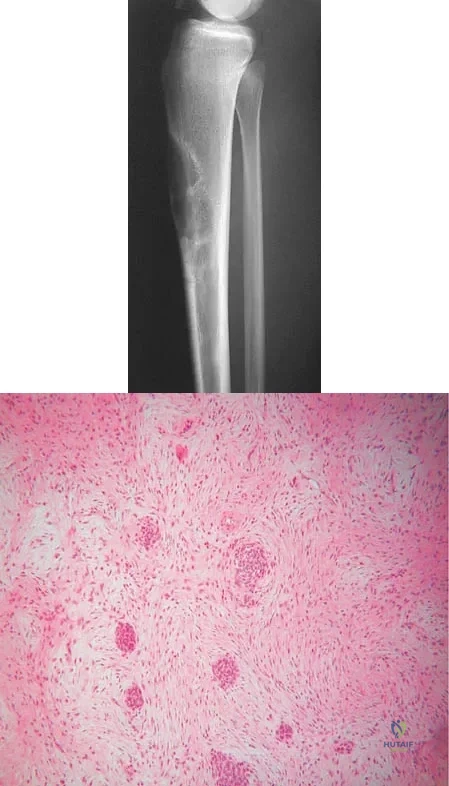

A 16-year-old girl has had anterior leg pain and a mass for the past 8 months. Figures 2a and 2b show a radiograph and an H & E histologic specimen. Which of the following disorders is believed to be a precursor of this lesion?

Explanation